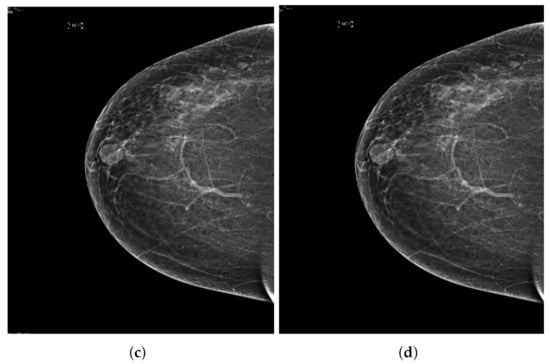

Computerized analysis of mammography is also challenging because one of the most important challenges is observing the pectoral muscles. The geometric shape of the pectoral muscles and their location depend on the mammographic images’ specific view [12,13]. There are two types of mammographic image views: the carnio-caudal (CC) view and the mediolateral oblique (MLO) view, and these views are shown in the Figure 1. The pectoral muscle on the CC view is semi-elliptical along the breast wall. In contrast, the MLO view covers most of the upper mammogram coverage and roughly corresponds to the overlapping right-angled triangle, as shown in Figure 1. Due to their appearance, both views suffered from low contrast, which made it difficult to see cancerous areas in some cases. Image enhancement requires correct observation and helps segment abnormal regions for disease classification. The quality of mammography images in terms of noise reduction and contrast enhancement is improved by using the image enhancement technique. The main purpose of implementing the image enhancement technique is to help the computerized breast cancer detection system to detect mammographic lesions with poor visibility and improve low contrast. Low contrast regions with small abnormalities are mostly hidden in the tissue of mammogram images, which makes it challenging to analyze the abnormal region, and also provides false detection.

Figure 1.

Representation of standard mammography views. The figure (a) represents the CC view of the right and left breast, and the figure (b) represents the MLO view of the right and left breast.